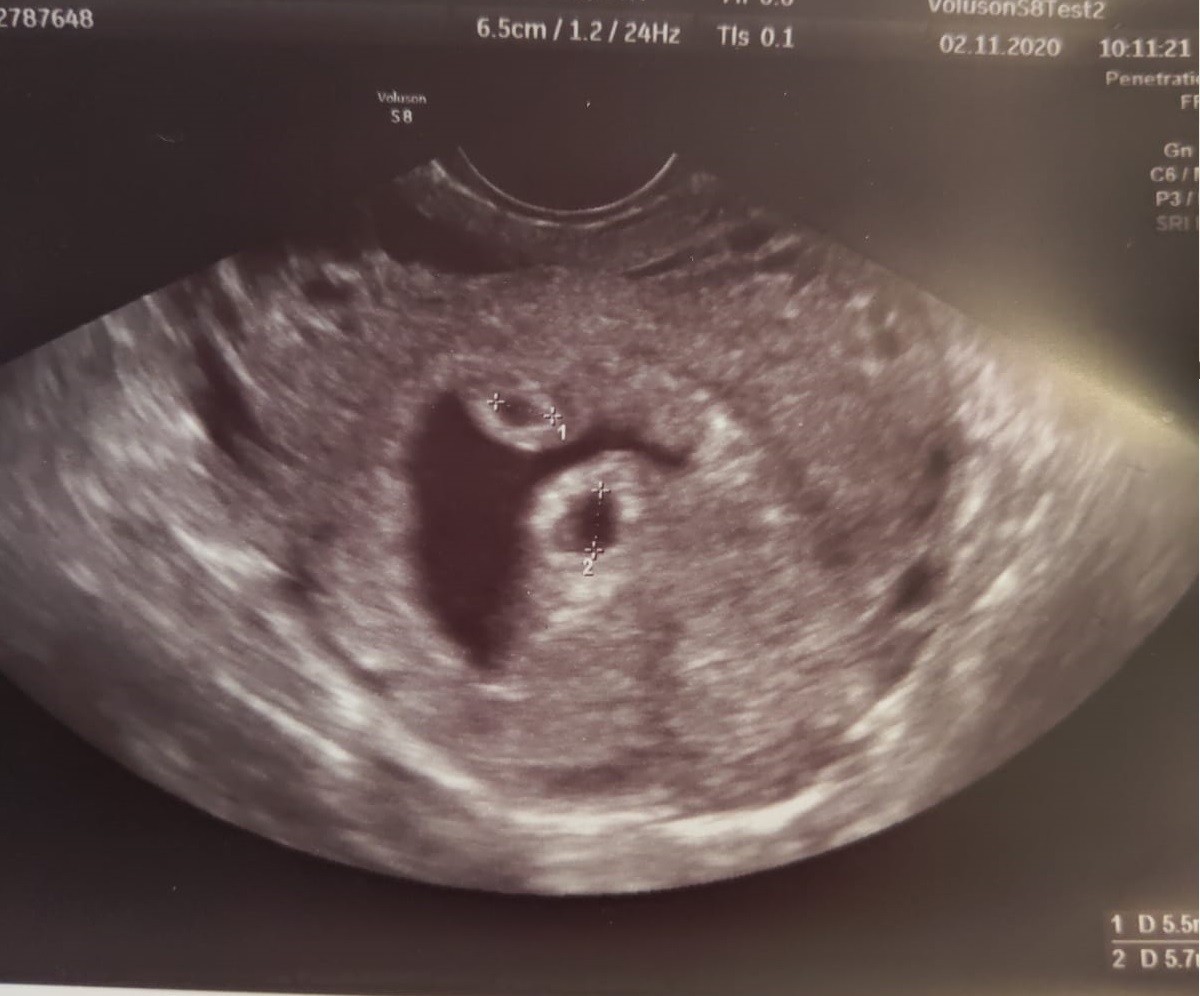

Wydaje mi sie, ze ta kropka jest troche za daleko i troche za blada (powinna być w środku czarna), gdyby były dwa lekarz by zauważył. Zwłaszcza, że liczba płodów to jest to na czym się na pierwszej wizycie bardzo skupiają, na tym zdjeciu widać tylko jednego dzidziusia, plamki, bąbelki to normalne rzeczy na USG.Druga bledsza kropka

Też tak myślę. Mam tylko nadzieję że to nie krwak. Moje siostry miały krwiaki w ciąży więc trochę się boję.Wydaje mi sie, ze ta kropka jest troche za daleko i troche za blada (powinna być w środku czarna), gdyby były dwa lekarz by zauważył. Zwłaszcza, że liczba płodów to jest to na czym się na pierwszej wizycie bardzo skupiają, na tym zdjeciu widać tylko jednego dzidziusia, plamki, bąbelki to normalne rzeczy na USG.

Drugi pecherzyk zawsze jest w miarę blisko na poczatku i wyraźnyTeż mialam tak, jak na zdjęciu od koleżanki.